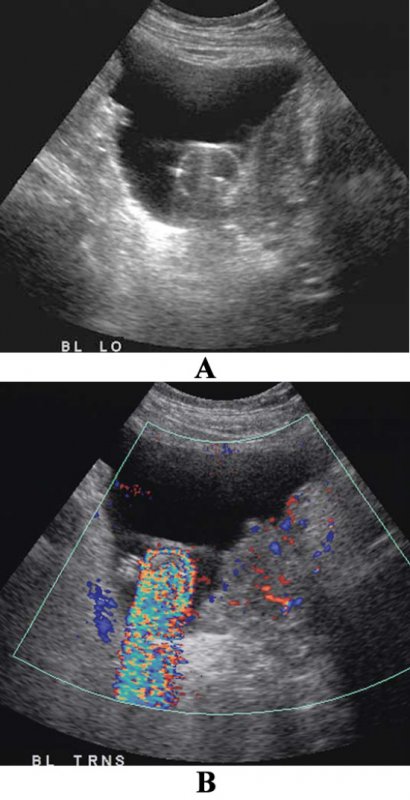

Артефакт ложного потока по сути является потоком реально жидкости, но не крови, например, амниотическая или асцитическая жидкость. В качестве примера ложного потока также можно привести струю в мочевом пузыре. Таким образом, используемый в повседневной практике термин «ложный поток» по сути является неправильным, поскольку более корректно применять термин «некровянной поток» (фото 3, 4, 5).

УЗИ брюшной полости: артефакт ложного потока при асците

Фото 5. УЗИ брюшной полости: артефакт ложного потока при асците. А – поперечное изображение в режиме серой шкалы через серповидную связку отмечается анэхогенная жидкость, которая ее окружает. В – цветная допплерография демонстрирует окрашенную жидкость

Артефакт ложного потока позволяет выявить течение жидкости или баллотирование (колебание или смещение анатомического образования в какой-либо полости организма) в местах скопления жидкостей (например, при абсцессе или гематоме, которые могут симулировать объемные образования).